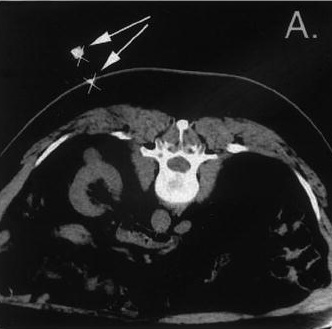

Examples of the robot position for three CT interventional procedures

使用集成的软件系统,可以选择靶目标的坐标,然后机器人可以提供介入器械到规定的位置。机器人的精确度有助于确保重叠消融和安全分离探针。机器人已应用于CT、MRI、X线透视,甚至超声的引导下的介入手术操作【98–100】。但是,精确标靶需要用于计划的图像病人图像配准和计算病人运动。所有这些都是面对导航和图像融合相同的挑战。 94. Marohn MR, Hanly EJ. Twenty-first century surgery using twenty-first century technology: surgical robotics. Curr Surg 2004; 61(5): 466–473